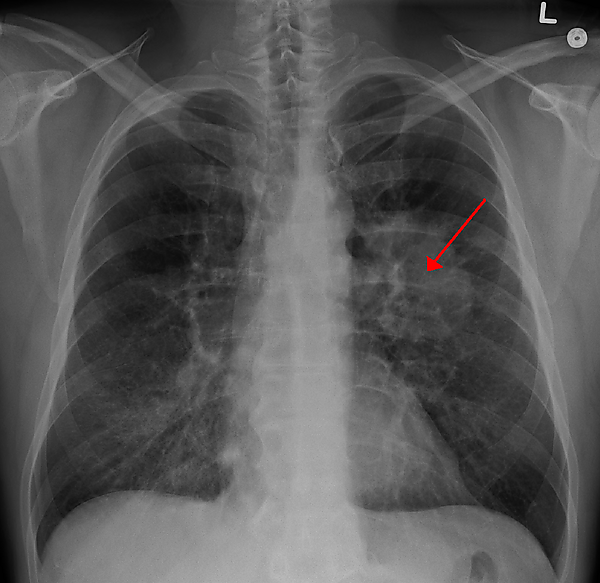

Рентгенологическое исследование является одним из основных методов диагностики опухолей лёгкого и позволяет своевременно обнаружить его у 80 % больных. В качестве скринингового метода используется флюорография, которая обычно проводится во время профилактических медосмотров. При выявлении изменений (солитарный лёгочный узел, ателектаз и т. д.) на флюорограмме или при наличии клинических показаний применяют рентгенографию в двух проекциях и компьютерную томографию. Кроме того, компьютерная томография является наиболее информативным методом диагностики метастазов в других органах.